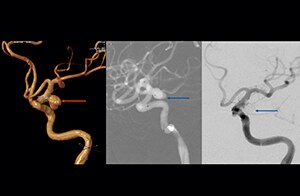

The Sixth Affiliated People’s Hospital, Shanghai Jiao Tong University (China), uses timeof-flight MR angiography (TOF MRA) to visualize cerebral aneurysms. The team has high confidence in their 3D TOF MRA method when imaging patients with small aneurysms.

“The 3D TOF MR angiograms are obtained by using 3D T1- weighted FFE sequences (TR 35 ms, TE 7 ms, flip angle 20 degrees, field of view 250 × 190 × 108 mm, matrix 732 × 1024, four slabs, 180 slices of 0.8 mm thickness, acquisition time 8:56 minutes). On our Achieva 3.0T MRI system with an 8-channel head coil, 3D TOF is easy to use and the background signal suppression is very good. Maximum intensity projections (MIPs) and volume-rendered images are reconstructed from the data. We use a single-artery highlighting method to reduce arterial overlay. The method can also be used for carotids or other small intracranial vessels.”

“Advances in MR imaging, the high SNR and spatial resolution of 3.0T, increasing observer experience and improved postprocessing techniques have improved the capabilities of MRA over the last decade. We found that 3D TOF MRA provides excellent images for the visualization of small cerebral aneurysms which enables us to accurately diagnose, and this accuracy appears to be similar to that obtained with DSA according to data from a 2014 study," [2] Dr. Li says. “Aneurysm location can influence how easy it is recognized. Infundibula can mimic aneurysms, adding to the difficulty of interpretation. On MIP images, small aneurysms can also be easily misinterpreted when the aneurysm overlaps with the vessel. This is why in our method we are viewing the images from multiple angles.” “In the hundreds of patients with aneurysms that we scanned, we saw no significant differences in accuracy, sensitivity or specificity among the locations. [2] We think this is the result of technical advances in image acquisition and postprocessing algorithms.”